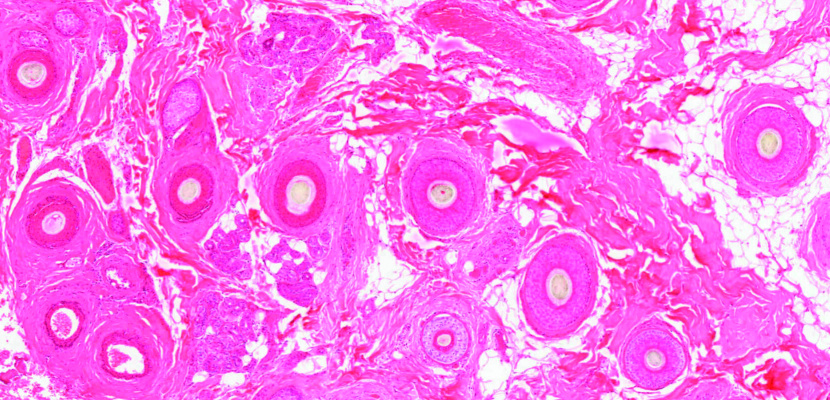

Microscope virtuel

Le site web de microscopie virtuelle de la Faculté de médecine permet d'observer des dizaines de coupes histologiques...

Microscopie à l'UNIGE

Activité organisée conjointement avec les enseignant-es et basée sur l'observation de coupes histologiques au...

Formation continue – Histologie du corps humain

Mise à jour de ses connaissances en histologie du corps humain (et comparaison possible avec d'autres espèces...